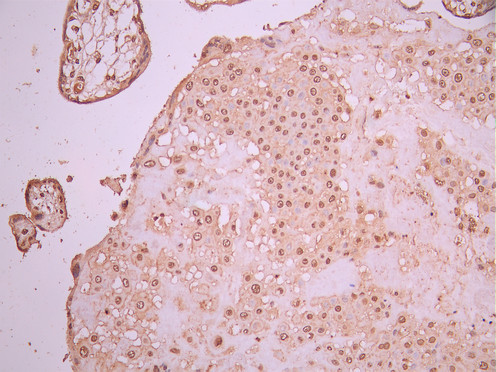

IHC image of CSB-RA896869MA2HU diluted at 1:50 and staining in paraffin-embedded human placenta tissue performed on a Leica BondTM system. After dewaxing and hydration, antigen retrieval was mediated by high pressure in a citrate buffer (pH 6.0). Section was blocked with 10% normal goat serum 30min at RT. Then primary antibody (1% BSA) was incubated at 4°C overnight. The primary is detected by a Anti-Human lgG, Fcy Fragment Specific labeled by HRP and visualized using 0.05% DAB.